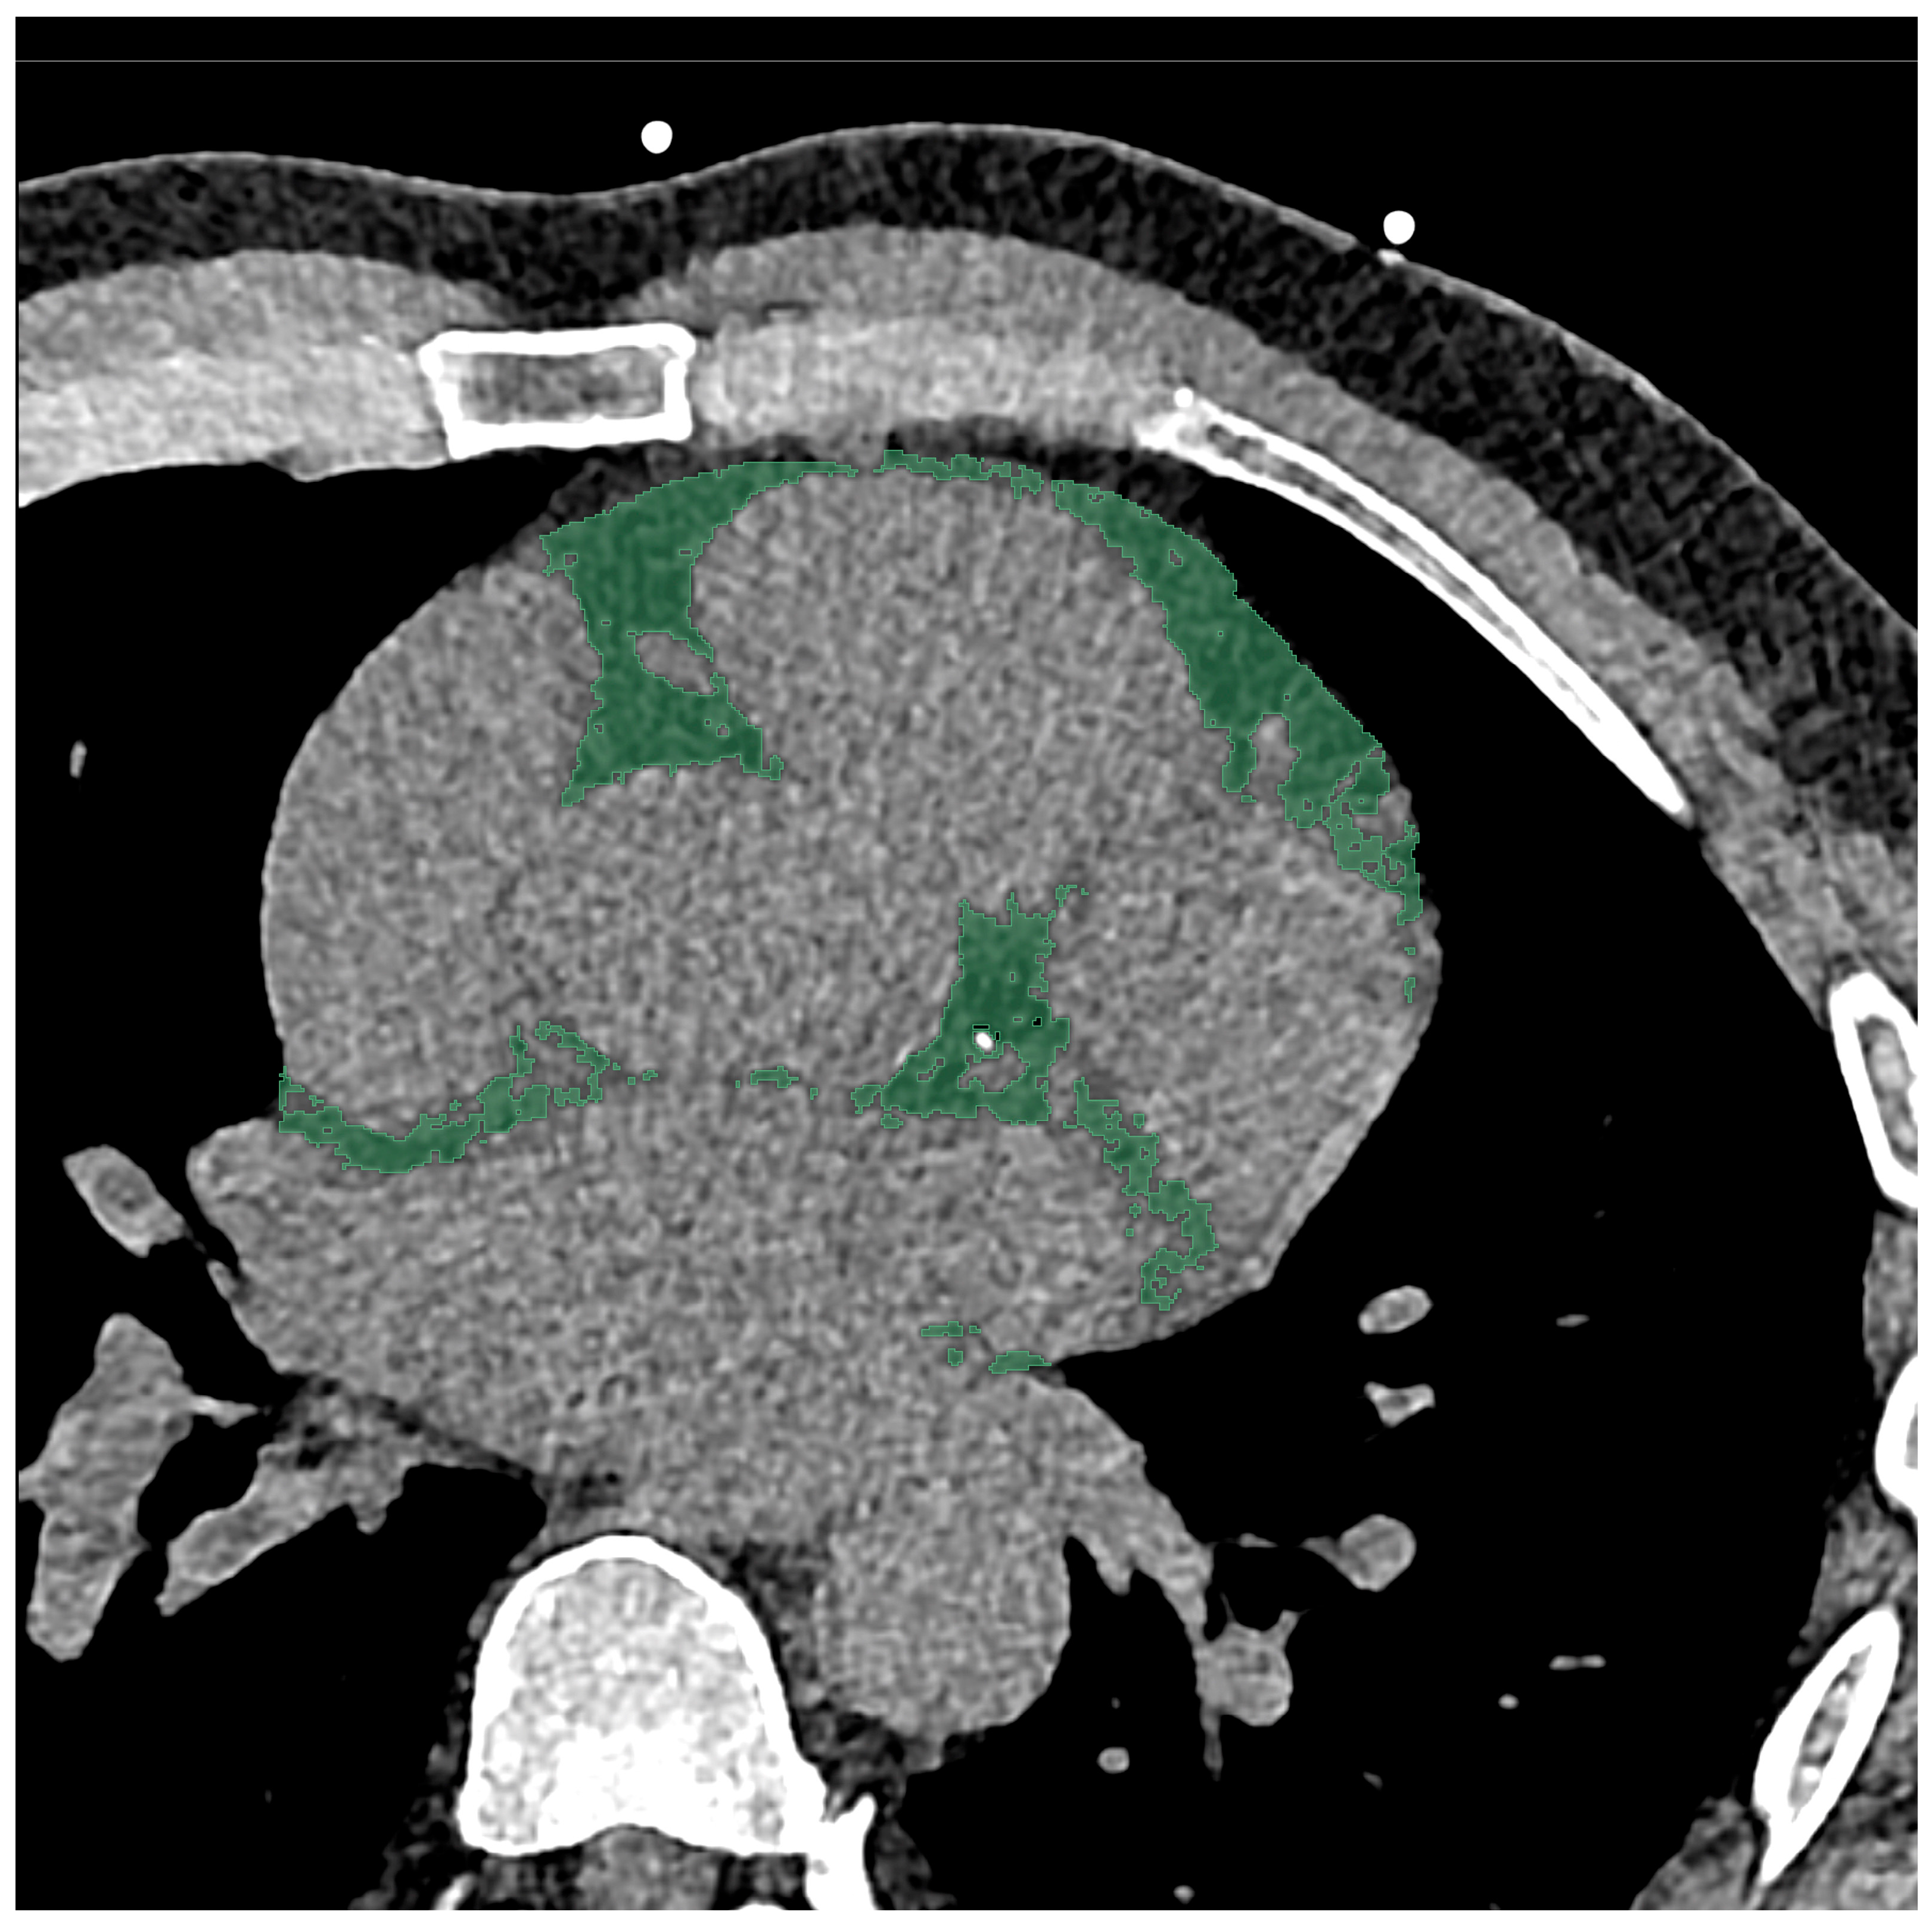

2.3. Chest CT Imaging Analysis

2.4. Radiomics Feature Extraction and Statistical Analysis